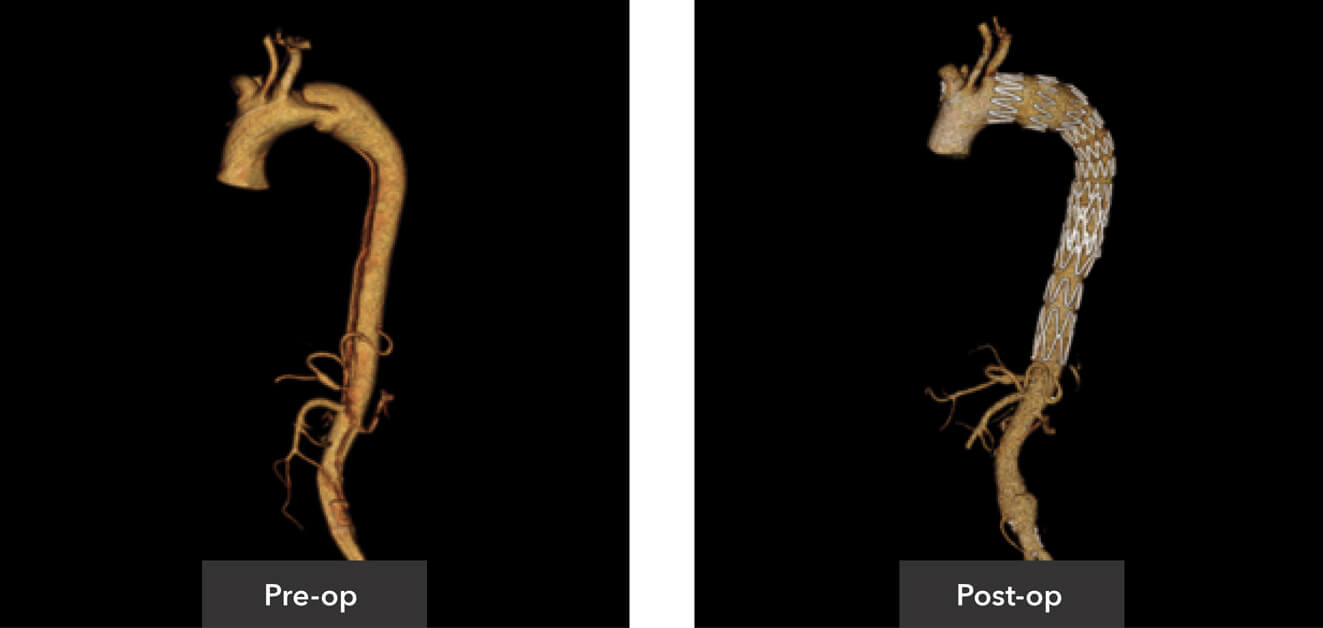

Pre-op/post-op Tera Recon imaging

Sagittal view pre-op/post-op CT imaging